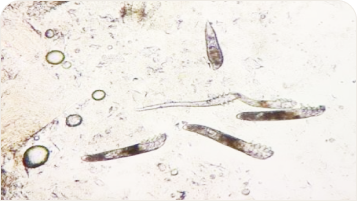

提供各種皮膚病診療,包括皮膚、指甲及毛髮疾患治療。設置窄波紫外線照光機治療白斑、乾癬、異位性皮膚炎等。